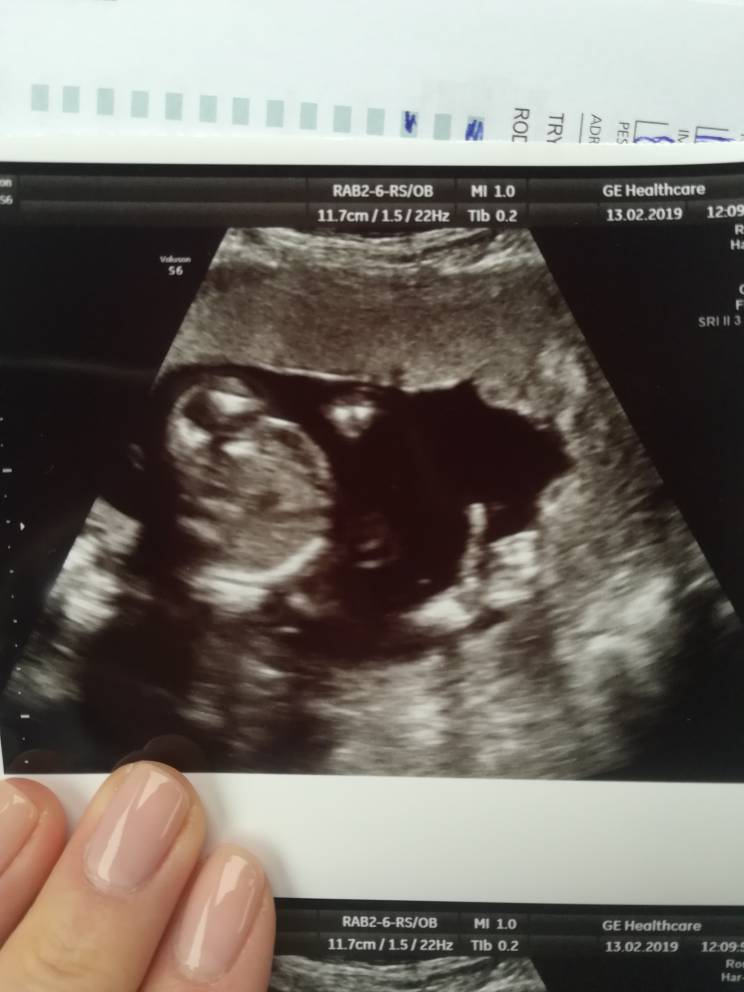

A ponizej focia corci... Spojrzcie w prawy dolny rog. Jest i okejka[emoji106][emoji106][emoji106][emoji106][emoji106]Zobacz załącznik 942472

I pani dr powiedziała, ze corcia na 100%. A Ona ostrozna z takimi ocenami... Wiec chyba moge rzucic sie w koncu na falbanki[emoji23][emoji23].